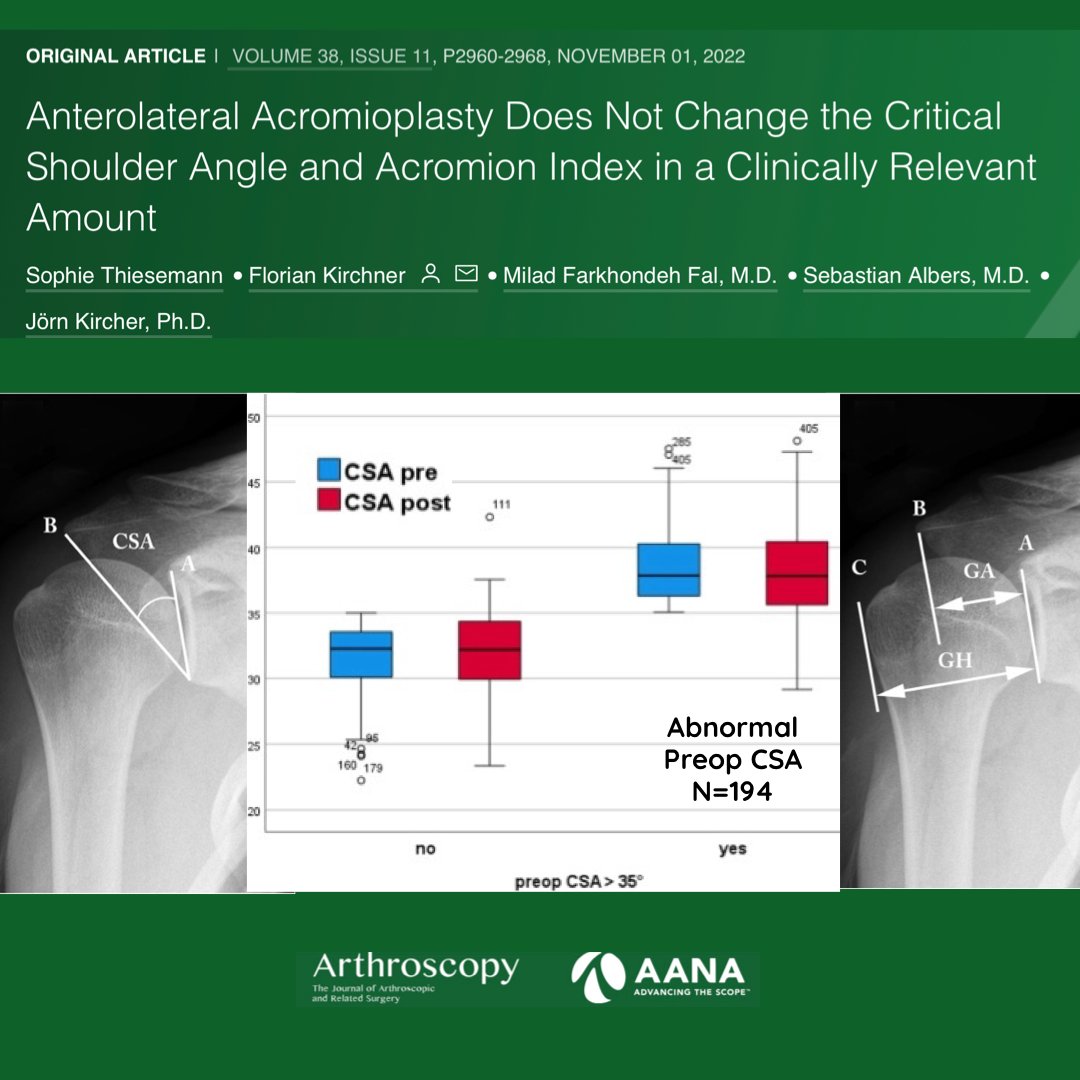

Brian Waterman, MD with his commentary on the clinical usefulness of classic anterolateral acromioplasty vs. lateral acromioplasty in cases of RTC tears with an increased critical shoulder angle. ow.ly/MS6550LGcgt